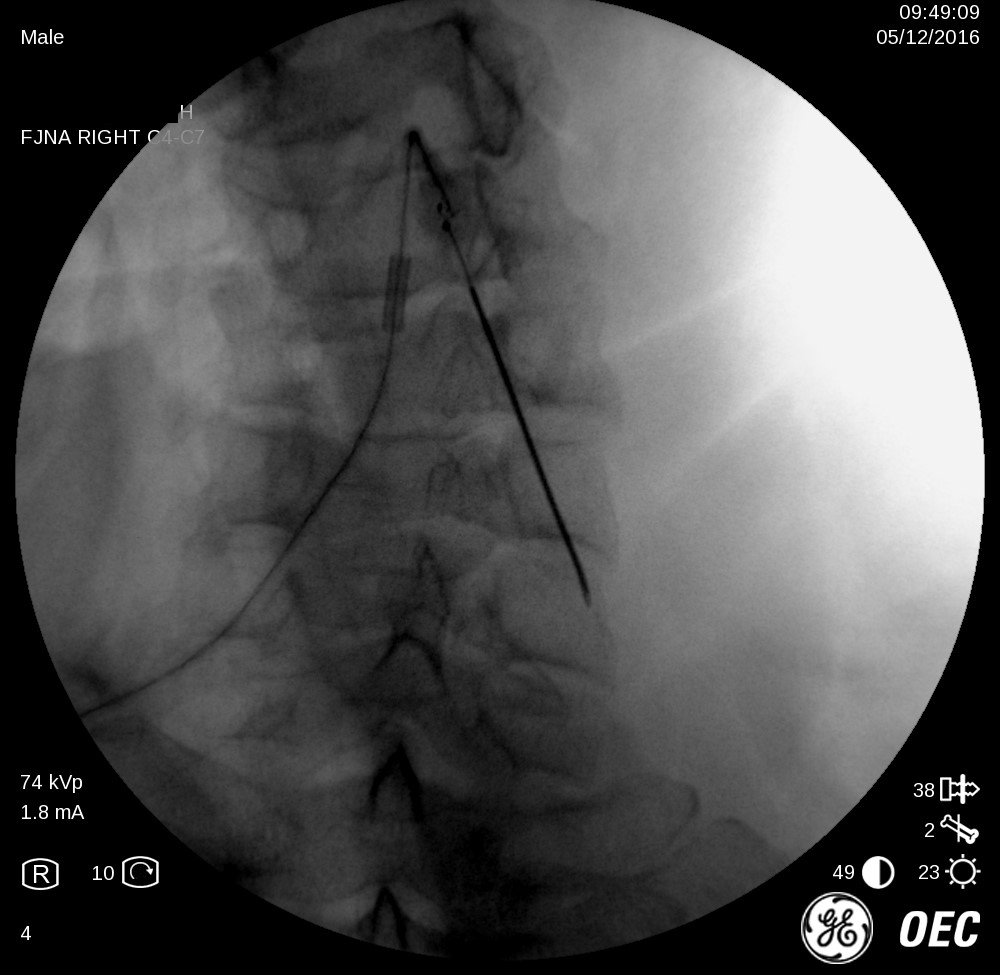

1-Facet-Denervation-Anatomage-Dr.-Hany-Wahib-Anatomy-Dept.-Ain-Shams-Univ.-1